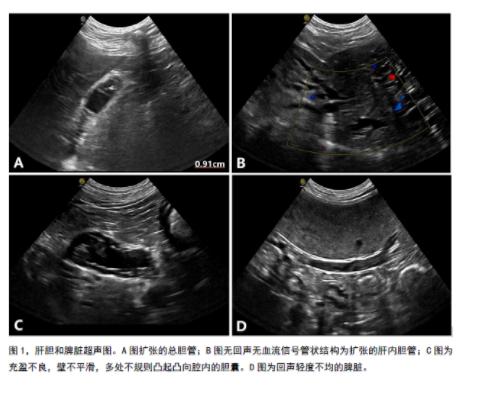

腹部超声检查:胆囊炎的影像学特征各不相同,超声可能发现胆囊壁增厚、不平滑、胆囊或胆管内中高回声沉积物、胆结石、肝外胆道扩张梗阻和胆囊气肿等。由于老年犬由于常见胆泥淤积,其超声征象与胆囊炎相似。该患犬超声发现肝内胆管和总胆管梗阻扩张,胆囊壁不平看,提示胆囊息肉/胆囊炎/胆泥附壁。CT提示胆囊炎伴肝内胆管和总胆管梗阻扩张,胆囊和总胆管内胆盐结晶,胆囊壁在延迟相增强,可能提示胆囊炎。